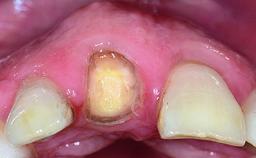

A 28-year-old patient presented at her general dentist’s office and complained about the appearance of her tooth 21. The patient had a history of trauma to this tooth. Endodontic treatment had been performed in the past and a crown placed on the tooth. A procedure to replace the old crown was performed by her dentist; however, a perforation on the middle third of the root occurred, and extraction of tooth 21 was suggested. Upon clinical and radiographic examination of the patient, who had been referred to us, replacement of tooth 21 by a dental implant appeared to be indicated.

Abutment Type Customized

Prosthesis Type FDP